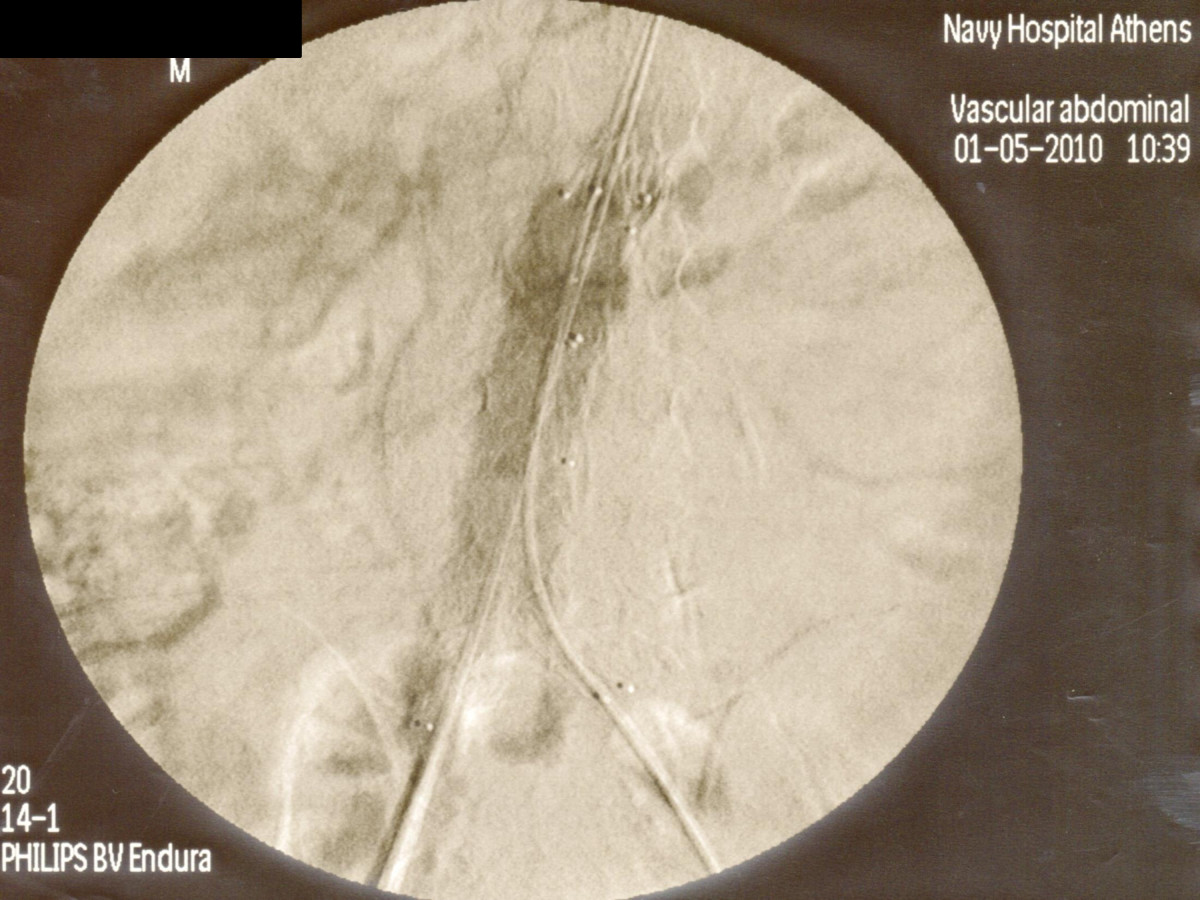

Ενδαγγειακή αποκατάσταση ανευρυσμάτων κοιλιακής αορτής

12ο Πανελλήνιο Συνέδριο Αγγειακής και Ενδαγγειακής Χειρουργικής

2010, Αθήνα